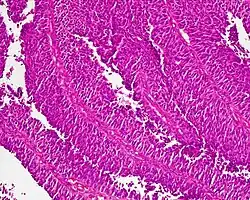

Gruczolakoraki (łac. adenocarcinomata)

Gruczolakoraki powstają najczęściej w przewodzie pokarmowym, gruczołach dokrewnych, trzustce, wątrobie, trzonie macicy, jajnikach, płucach, gruczole krokowym, śliniankach, sutku, nerkach.

Gruczolakoraki można podzielić na podstawie obrazu histologicznego, uwzględniając m.in.: